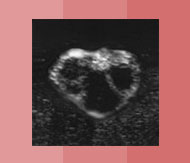

Besamung Verhalten Verhalten in der Vorbrunst In der Vorbrunst beginnt das Tier unruhig zu werden (Flehmen, Kopf auflegen). Brünstig werdende Tiere legen oft den Schwanz zur Seite, insbesondere, wenn sie von anderen Tieren beschnuppert werden. Für eine Besamung ist es zu früh, aber man muss gut beobachten! Verhalten in der Brunst Zu Brunstbeginn kann es rund um die brünstig werdende Kuh sehr unruhig werden. Besonders auf der Weide ist das gut sichtbar. Mitte der Brunst: Die Kuh duldet andere Kühe, wenn diese ihr aufspringen. Sie zeigt den Duldungsreflex. Für eine Besamung ist es noch zu früh! Aber die Kuh kann bereits beim Besamer angemeldet werden. Im Stall kann man hochbrünstige Tiere am stieren Blick, gestellten Ohren und durchgekrümmten Rücken manchmal gut erkennen. Verhalten in der Nachbrunst Jetzt is der ideale Besamungszeitpunkt! Das Tier wird wieder ruhiger und duldet andere Tiere nicht mehr beim Aufsprungversuch. Aber: Beim Abbluten ist es zu spät für die Besamung! Verhalten in der Zwischenbrunst In der Zwischenbrunst verhalten sich die Tiere unauffällig. 2-3 unruhige Phasen von einigen Stunden sind möglich. Eine Besamung macht hier keinen Sinn! Eierstock Eierstock in der Vorbrunst Der Gelbkörper bildet sich zurück. Das dominate Eibläschen hat einen Durchmesser von gut 1cm. Das Eibläschen ist glatt und prall („uhrglasartig“). Der Eierstock in der Brunst Das Eibläschen wächst in kurzer Zeit heran und ist prall. Der Gelbkörper von der letzten Brunst kann noch spürbar sein. Das Eibläschen erreicht einen Durchmesser von ca. 1.5 bis 2 cm und wird weicher. Jetzt hat das Eibläschen seine maximale Grösse erreicht. Kurz bevor es springt, wird es weich. Der Eierstock in der Nachbrunst Zu Beginn der Nachbrunst springt das Eibläschen. Das Eibläschen wird vom Eileitertrichter aufgefangen. Im Eileiter findet die Befruchtung durch den Samen statt. Der Eierstock in der Zwischenbrunst Der Gelbkörper hat oft eine Form wie ein Champagnerzapfen. Während eines Zyklus können sich 1-2 Eibläschen auf dem Eierstock an- und wieder zurückbilden. Der Gelbkörper bildet sich zurück, wenn von der nichtträchtigen Gebärmutter Prostaglandin gebildet wird. Gebärmutter & Scheide Gebärmutter u. Scheide in der Vorbrunst Die Spannung in der Gebärmuttermuskulatur nimmt zu. Der Muttermund beginnt sich zu öffnen. Die Scheidenschleimhaut wird wieder feucht und rötet sich. Gebärmutter u. Scheide in der Brunst Die Gebärmuttermuskulatur zieht sich in der Brunst maximal zusammen. Die Gebärmutter ist daher klein und fest. Die Schleimhaut in der Scheide erscheint blassrosa und feucht und der Muttermund kann deutlich offen sein. Fadenziehender klarer Schleim kommt aus der Scheide. Gebärmutter u. Scheide in der Nachbrunst Die Muskulatur der Gebärmutter entspannt sich. Das Abbluten kann als guter Anhaltspunkt auf dem Brunstkalender festgehalten werden. Die Schwellung der Schamlippen geht zurück. Gebärmutter u. Scheide in der Zwischenbrunst Die Muskulatur der Gebärmutter ist entspannt und wenig kontrahiert. Der Muttermund ist fest verschlossen und die Scheidenschleimhaut ist wenig feucht und blass. Die Schamlippen sind gefältelt. Hormone Hormone in der Vorbrunst Hormone aus dem Zwischenhirn (GnRH) und der Hirnanhangsdrüse (FSH) werden in die Blutbahn abgegeben. Das follikelstimulierende Hormon FSH bewirkt die letzte Reifung des dominanten Eibläschens. Das dominante Eibläschen produziert das Brunsthormon (Östrogen). Hormone in der Brunst Das Brunsthormon wird vom Eibläschen produziert. Das Brunsthormon ist verantwortlich für das typische Verhalten der Kuh in der Brunst und die sichtbaren Veränderungen am Geschlechtstrakt. Der Anstieg des luteinisierendem Hormons LH führt zum Eisprung am Ende der Hauptbrunst oder bereits zu Beginn der Nachbrunst. Hormone in der Nachbrunst Das luteinisierende Hormon bewirkt den Eisprung und die Bildung von Gelbkörpergewebe. Die Produktion vom Trächtigkeitshormon beginnt. Der Spiegel vom Brunsthormon ist wieder tief. Hormone in der Zwischenbrunst Der Gelbkörper bildet im Zyklus während ca. 14 Tagen das Trächtigkeitshormon Progesteron. Bei einer Trächtigkeit bildet die Gebärmutter dank Signal des Embryos um den 16. Zyklustag kein Prostaglandin F2alpha und der Gelbkörper bleibt bestehen. Ohne Befruchtung bildet die Gebärmutter Prostaglandin F2alpha, der Gelbkörper geht zu Grunde und ein neuer Zyklus beginnt. Bedienungsanleitung Vorbrunst Brunst Nachbrunst Zwischenbrunst